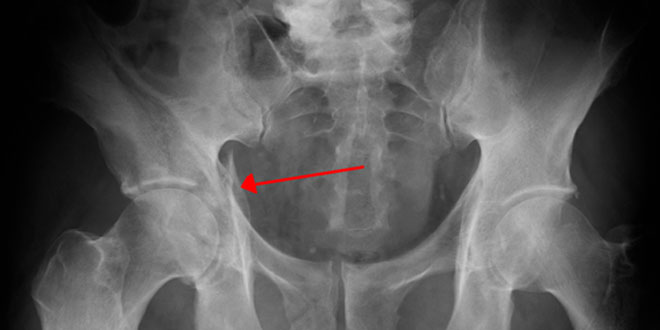

والنخرة الجافة أو التنخر اللاوعائي لرأس الفخذ حسب الاختصاصي تموت في رأس عظم الفخذ ناتج عن انقطاع التروية الدموية المغذية له يؤدي إلى حدوث تشوهات وانهدام وتغير في الشكل التشريحي له وبالتالي حدوث تغير في هيكلة مفصل الورك وحركته.

وعن العلاج بين جراح العظيمة توفر طرق علاجية متنوعة وذات فعالية عالية لمنع تطور التنخر في حال التشخيص المبكر منها تثقيب رأس الفخذ بعمل جراحي بسيط مع إجراء تطعيم لمكان التثقيب بطعم عظمي ذاتي من المريض نفسه وحاليا “أثبتت فعالية حقن البلازما الغنية بالصفيحات أثناء التثقيب” موضحا أن العلاج يجب أن يترافق مع راحة الطرف التامة واستخدام المميعات الدموية والمسكنات والعلاج الفيزيائي.

وفي الحالات المتقدمة التي تنتهي بتشوه راس الفخذ والتنكس المفصلي ذكر الاختصاصي أن العلاج الجراحي باستبدال مفصل الورك بآخر صنعي هو الحل المناسب.